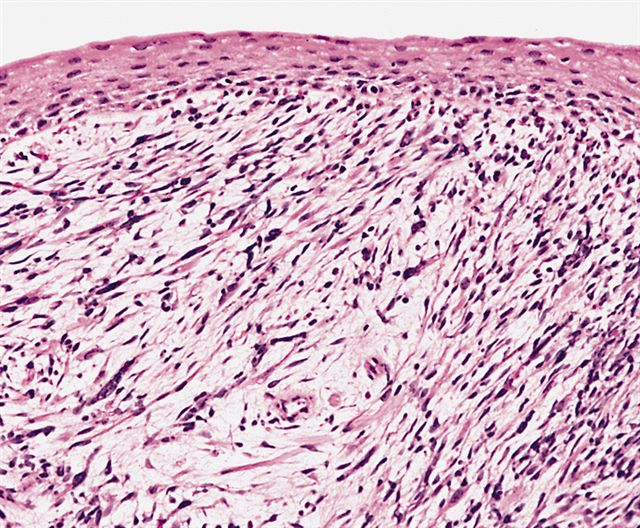

- Botryoid variant frequently shows a cambium layer: a hypercellular zone immediately beneath the epithelial surface

- Cells are undifferentiated, round or spindled with minimal cytoplasm, frequent mitotic figures

- Deeper layers of the tumor are typically less cellular but overall conform to the histology of embryonal rhabdomyosarcoma (ERMS) with variation by region

Microscopic (histologic) images

AFIP images - botryoid variant

- Botryoid embryonal rhabdomyosarcoma (sarcoma botryoides) only occurs in certain locations, specifically beneath mucosal epithelial lined viscera, such as the bladder, biliary tract, vagina or upper respiratory tract, extrahepatic bile ducts or near a space; rarely in eyelid or anal region

- Often has a grape-like (botryoid) growth pattern

- Botryoid variant has a particularly good prognosis, although may have late relapse (Zhonghua Bing Li Xue Za Zhi 2004;33:225, Pediatr Blood Cancer 2008;51:140)

- Botryoid variant: conservative surgery plus radiation and chemotherapy (Int J Gynecol Cancer 2008;18:190)

- Botryoid variant: resembles cluster of grapes or allergic nasal polyp, fleshy nodular polypoid projections of variable size into lumen